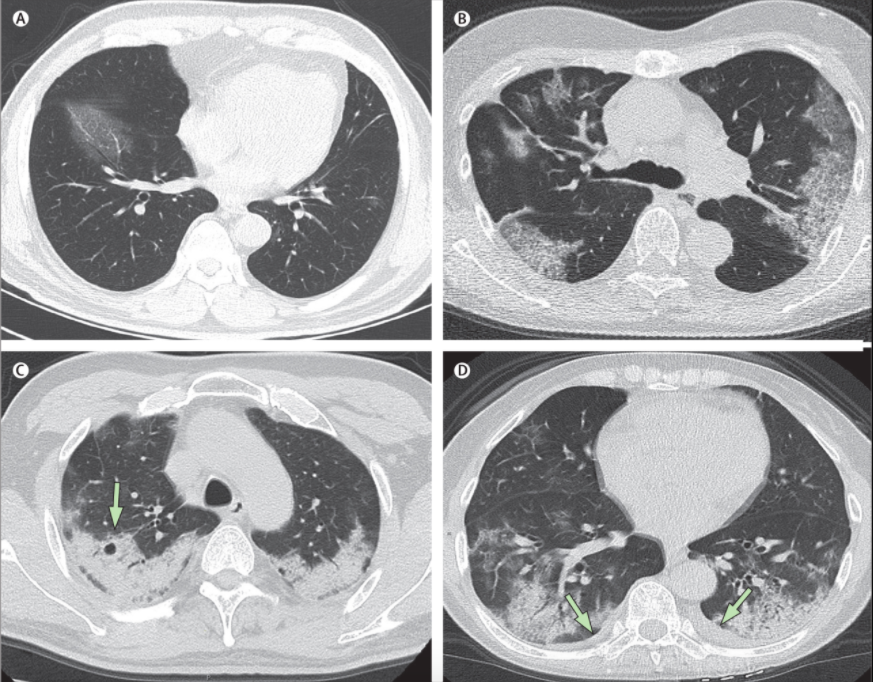

Patterns of COVID19 pneumonia on CT

Transverse thin-section CT scans in patients with COVID-19 pneumonia. (A) 56-year-old man, day 3 after symptom onset: focal ground-glass opacity associated with smooth interlobular and intralobular septal thickening in the right lower lobes. (B) 74-year-old woman, day 10 after symptom onset: bilateral, peripheral ground-glass opacity associated with smooth interlobular and intralobular septal thickening (crazy-paving pattern). (C) 61-year-old woman, day 20 after symptom onset: bilateral and peripheral predominant consolidation pattern with a round cystic change internally (arrow). (D) 63-year-old woman, day 17 after symptom onset: bilateral, peripheral mixed pattern associated with air bronchograms in both lower and upper lobes, with a small amount of pleural effusion (arrows).